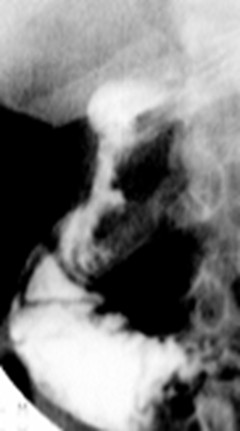

Deformation en deux

ailes d' ulcere bulbaire avec niche au milieure

.( fleche noire ) |

Image TOGD de estoma en decubitus OAD .

Deformation en deux ailes du bulbe . |